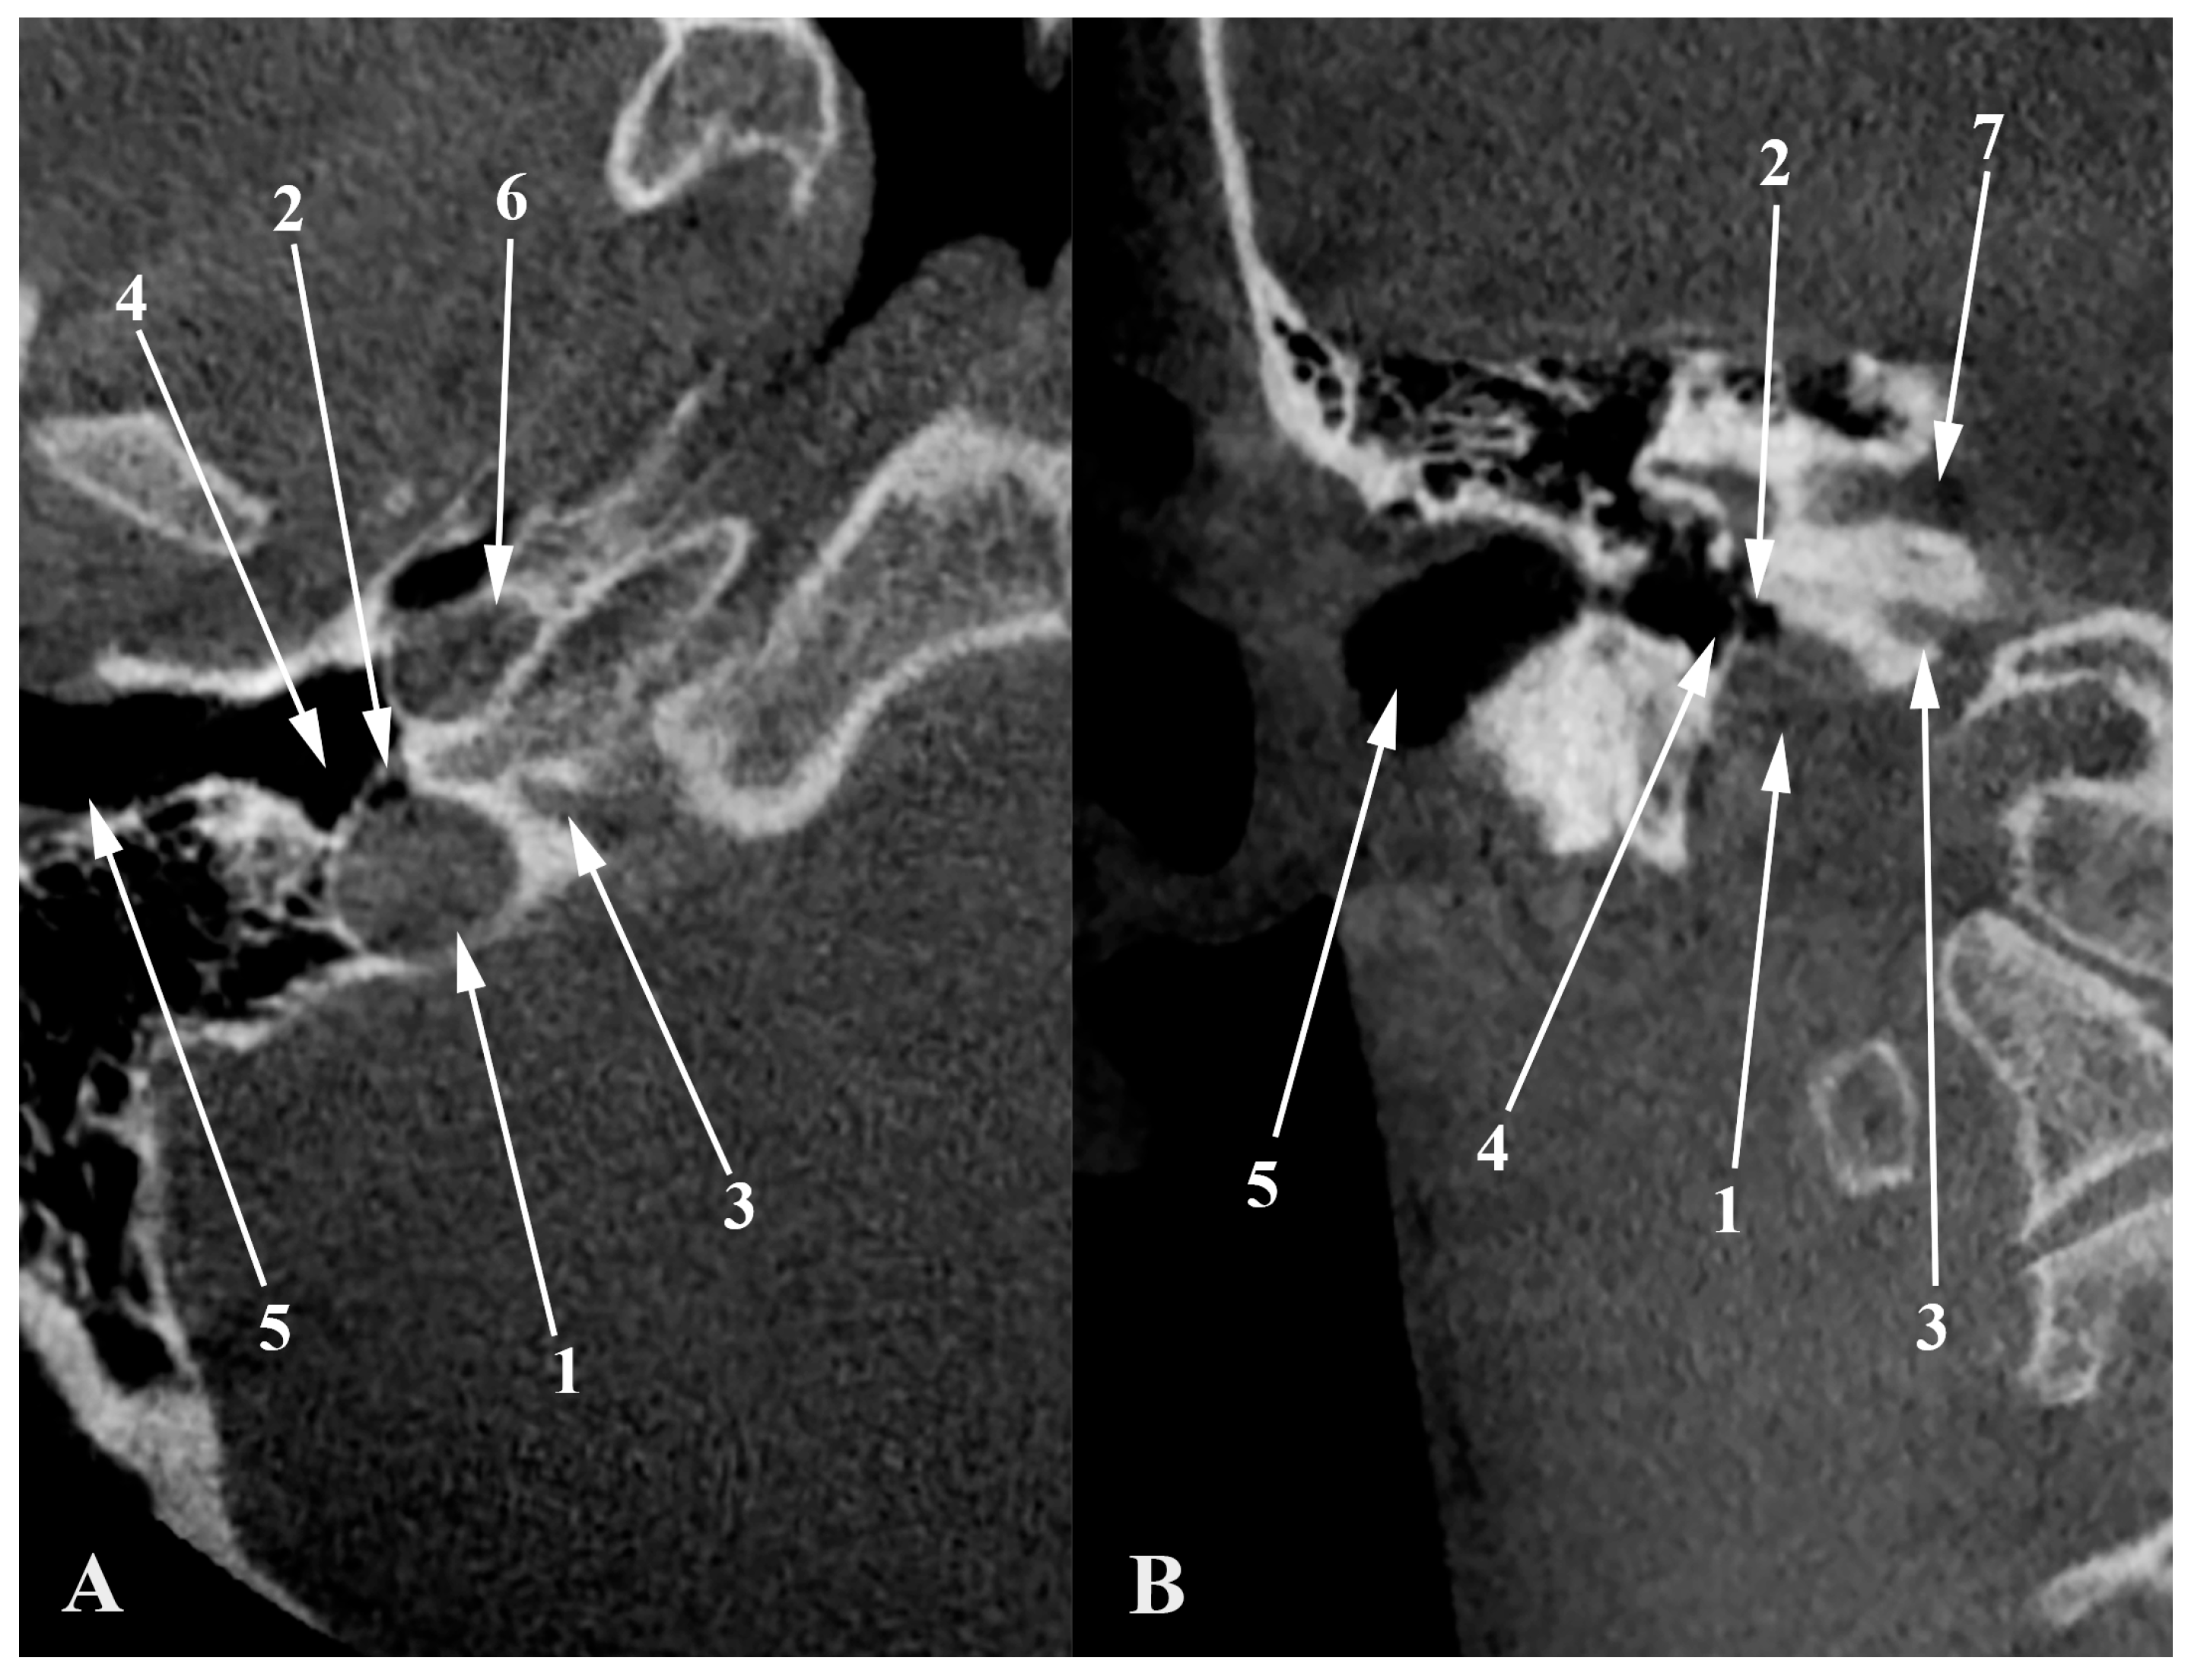

4. High Jugular Bulb

5. Dehiscent Jugular Bulb